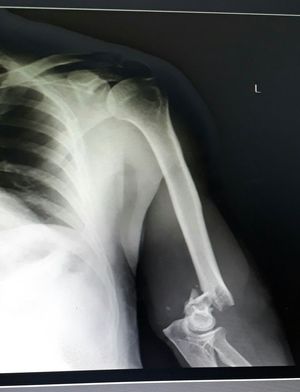

Humerus fracture !

Radiology

Xray

Fractures

Elbow

Supracondylar fracture of humerus